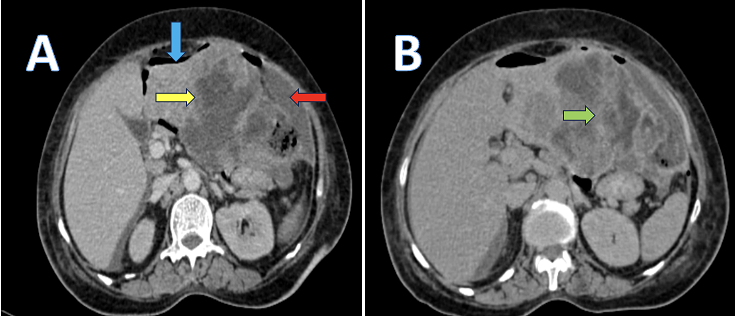

A 70-year-old female presented with complaints of abdominal pain and nausea for several days, without any known comorbidities or prior abdominal surgery. On examination, there was mild tenderness in the upper abdomen without palpable mass or hepatomegaly. Laboratory parameters, including liver function tests, were within normal limits. To further evaluate the cause of pain, Contrast enhanced computed tomography (CECT) of the abdomen and pelvis was performed. Imaging revealed an ill-defined, multiloculated, heterogeneously enhancing lesion in the gastrohepatic region involving the left lobe of the liver (image A, yellow arrow) measuring approximately 9.6x15.3x13.9cm. The lesion showed loss of fat planes with the adjacent stomach, pancreas and spleen with delayed peripheral enhancement (image B, green arrow) and involvement of left branch of portal vein. Surrounding hepatic arterial hypertrophy was also noted. Associated findings included subdiaphragmatic air fluid collection (image A, red arrow) and free intraperitoneal air (image A, blue arrow), suggesting rupture of the lesion. Mild ascites and perihepatic lymphadenopathy were also noted. The imaging features -particularly the exophytic growth from the gastric wall, heterogenous enhancement and contiguous hepatic involvement-were suggestive of a ruptured gastrointestinal stromal tumor (GIST). Surgical resection was performed, and histopathological examination confirmed the diagnosis of GIST, showing spindle shaped tumor cells positive for CD117 (c-KIT) and DOG1 immunomarkers. Gastrointestinal stromal tumors are the most common mesenchymal tumors of gastrointestinal tract, typically originating from the interstitial cells of Cajal and frequently associated with KIT or PDGFRA gene mutations. This case underscores the pivotal role of CECT in identifying complex gastrohepatic mass and their complications, guiding timely surgical management. Ruptured GISTs are rare but clinically significant due to the risk of peritoneal dissemination and recurrence. Early radiological diagnosis, and prompt surgical management, and histopathological confirmation remain key to favorable clinical outcomes.